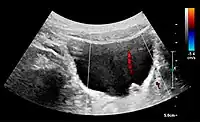

Doppler ultrasound (US) of a normal adult kidney with the estimation of the systolic velocity (Vs), the diastolic velocity (Vd), acceleration time (AoAT), systolic acceleration (Ao Accel) and resistive index (RI). Red and blue colors in the color box represent flow towards and away from the transducer, respectively. The specrogram below the B-mode image shows flow velocity (m/s) against time (s) obtained within the range gate. The small flash icons on the spectrogram represent initiation of the flow measurement.[1]

Doppler ultrasonography of the kidney is widely used, and the vessels are easily depicted by the color Doppler technique in order to evaluate perfusion. Applying spectral Doppler to the renal artery and selected interlobular arteries, peak systolic velocities, resistive index, and acceleration curves can be estimated (Figure 4) (e.g., peak systolic velocity of the renal artery above 180 cm/s is a predictor of renal artery stenosis of more than 60%, and a resistive index, which is a calculated from peak systolic and end systolic velocity, above 0.70 is indicative of abnormal renovascular resistance).[1]